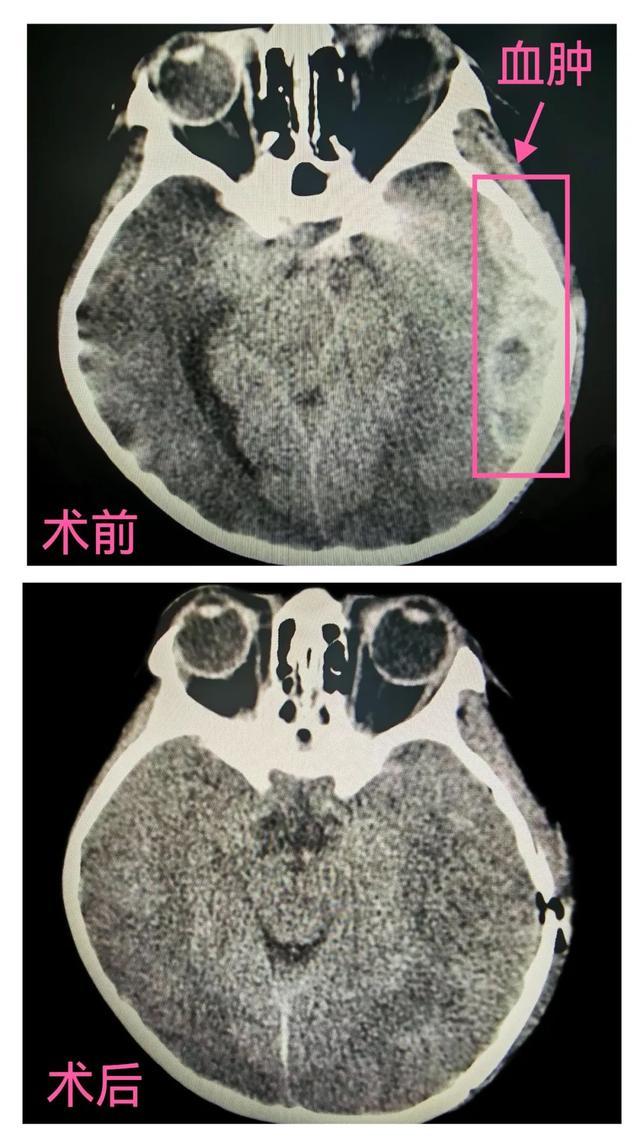

近日,6岁的童童在下课期间不慎和同学相撞,跌倒后头部受伤,当时仅有头痛头晕,也没重视。3小时后童童头痛症状加重,同时出现恶心呕吐,家属赶紧送入新宁县人民医院,头颅CT发现硬膜外有一大约10ml的血肿,以硬膜外血肿收入神经外科,立即积极治疗。

入院仅1小时余,童童意识障碍逐渐加深,并出现左侧瞳孔逐渐散大,形成脑疝了!紧急复查头颅CT硬膜外血肿明显增大约为70ml,情况十分危急!需要紧急手术清除颅内血肿!

科室迅速启动快速抢救反应小组,科主任陈伟国带领神经外科团队在30分钟内完成手术准备,在麻醉医生的密切配合下,为童童行急诊“左侧颞顶部开颅血肿清除+静脉窦修补+颅骨整复术”,成功清除血肿并修补破裂的静脉窦,手术顺利!

术后第一天童童意识障碍程度明显好转,能理解语言及配合动作。经医护人员精心指导快速康复,童童状态日渐恢复。